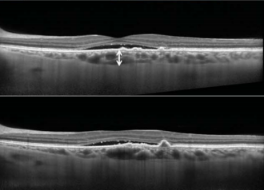

光学相干断层扫描(OCT)

显示:右眼黄斑结构基本正常,中心凹下脉络膜厚度155μm;左眼黄斑中心凹存在视网膜下积液(SRF),其下方可见小范围新生血管导致的色素上皮脱离,中心凹下脉络膜厚度280μm。值得注意的是,新生血管组织区域正下方可见显著局灶性脉络膜增厚伴大管径血管扩张,且该区域脉络膜毛细血管层和Sattler层结构消失(图2)。由于存在新生血管组织,因此排除了急性CSC的诊断。

图2,左眼黄斑中心凹存在SRF,其下方可见小范围新生血管导致的色素上皮脱离,中心凹下脉络膜厚度280μm。